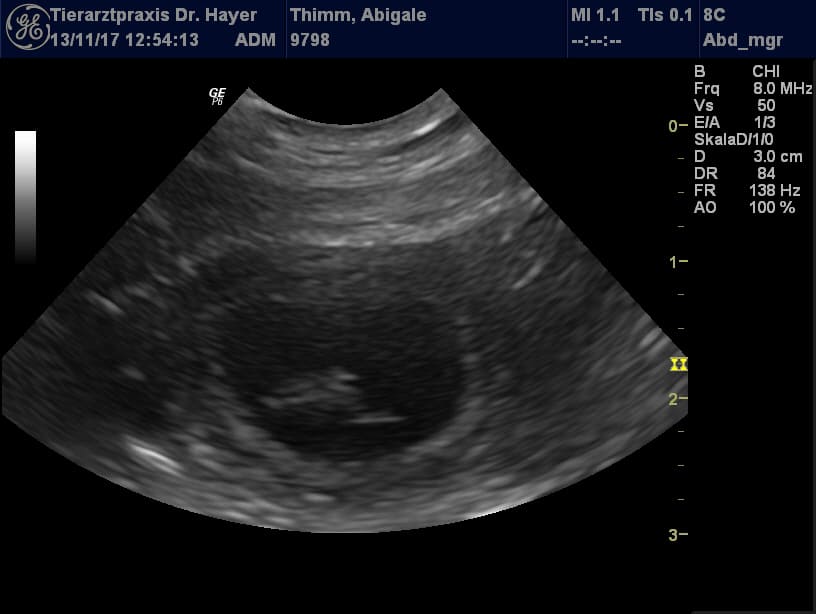

Heute waren wir zum Ultraschall und konnten einen ersten kleinen Blick auf unsere C-chen werfen. Abby geht es super. So ein schönes Geschenk zu ihrem vierten Geburtstag :-). Ich freue mich sehr auf die kommende spannende Zeit und hoffe, dass alles so problemlos weiter läuft.

Geburtstermin ist um den 22. Dezember